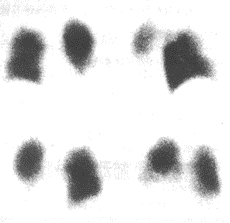

發生率約75%。開始於缺氧導致的呼吸急促及隨後的過度換氣,紫紺有時不會出現,但有時可能成為FES的早期體徵。涉及肺的FES病人大部分PaO2水平低於6.67kPa,如果肺的條件惡化,就可能合併呼吸困難和代謝性酸中毒。部分病人有咯血。胸部X線片示兩肺大塊斑片狀陰影,稱之為“暴風雪樣”改變,尤其在肺的上中部多見。

脂肪栓塞綜合徵--X線1呼吸支持療法不完全型或部分症候群:可以鼻管或面罩給氧,使氧分壓維持在9.3-10.7kPa(70-80mmHg)以上即可,創傷後3-5天內應定時血氣分析和胸部X線檢查。